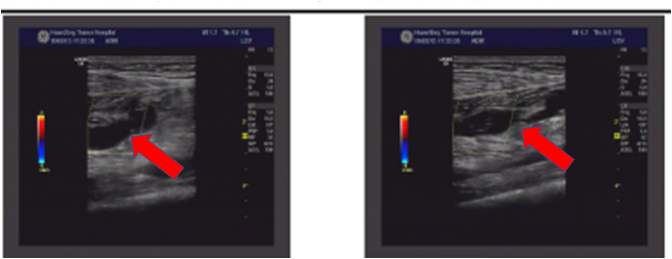

右颈及右锁骨上探及多个低回声,大者位于锁骨上,约2.2X1.3cm,周边可见少许血流信号。

2019.03.06我院上肢血管超声提示:双颈内静脉、右锁骨下静脉、腋静脉、肱静脉未见血栓征象。